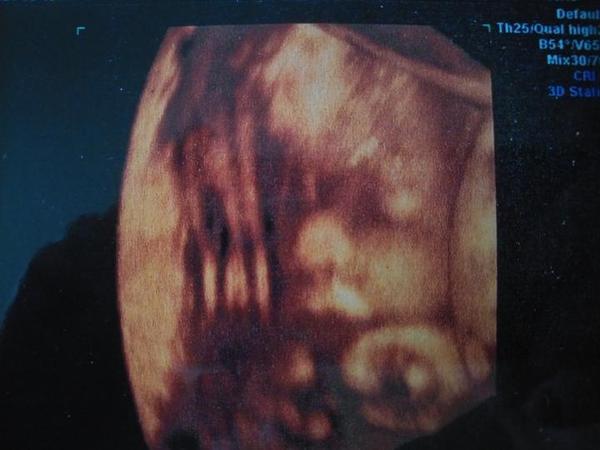

@tercasv ony ty cizí fotky na internetu jsou něco jiného, než když pak člověk vidí toho svého cvrčka 🙂 Mě tedy zase tak moc neoslovily přímo ty fotky - byť se nám povedly docela hezky, ale líbil se mi ten zážitek. Je vidět, jak se tam miminko tváří, jak zívá, dělá ksichtíky........🙂

Za mě fajn cesta do hlubin ...maminčina bříška - moc me bavilo, když jsem pak našla fotku ze 3D a fotku reálnou, které byly témeř totožné - tvář, výraz......

@tercasv ano určitě to za to stojí. Já byla několikrát, ještě lepší je 4D video nahrávka. Miminka ostatních se ti líbit nemusí, je to normální. Nechovás k nim žádný citový vztah. Tohle je vaše miminko, které milujete a určitě je to do budoucna krásná vzpomínka.

@tercasv Ja od toho moc neocekavala, premluvil me manzel, ze to zkusime, ze bychom treba litovali. Malej se nechtel ukazat oblicejem, takze jsme si dobre prohledli jeho zadek a naprosto presne vedeli, ze to bude kluk🙈 Pak se ale ukazal a stalo to za to. Mam fotku, kterou mam stale vytavenou na stole a rada se koukam, jak si byl po narozeni podobny, vcetne jeho mimiky😀 U me to tedy predcilo ocekavani, nejen ten vysledek, ale i ten zazitek byl fajn😀.